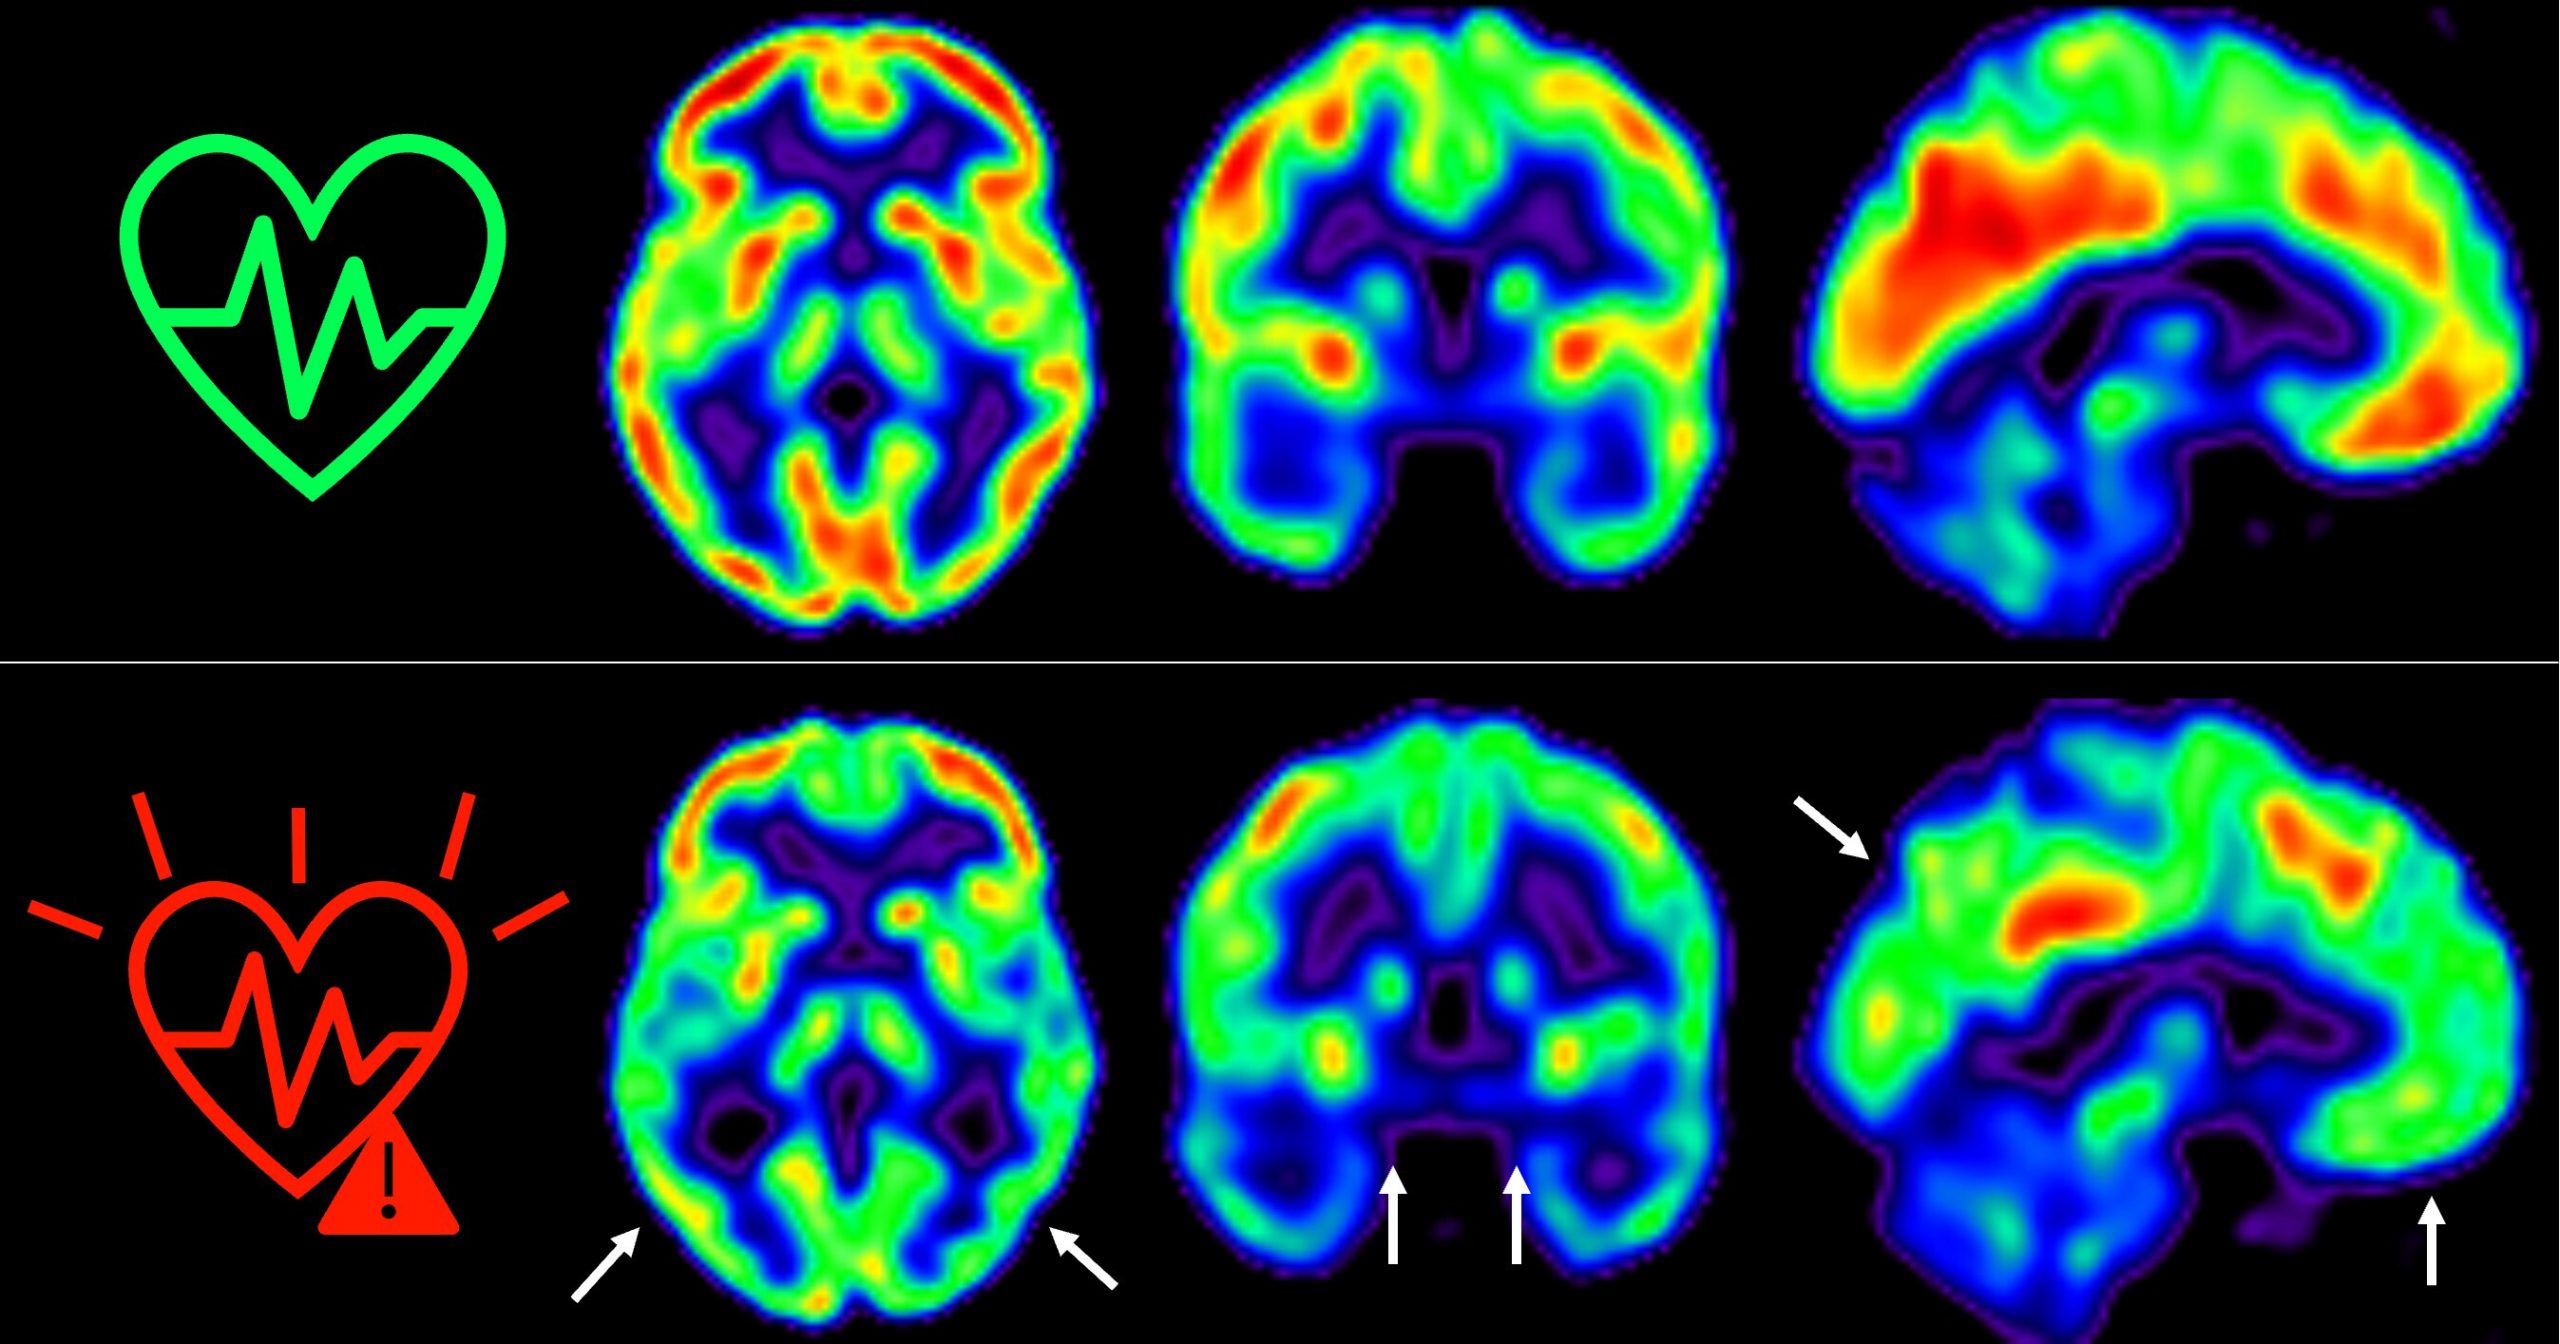

Esto se ha medido a través de técnicas de imagen como tomografía por emisión de positrones (PET). Este factor es un indicador de salud.

Las imágenes representan la captación de glucosa en cerebro medida por tomografía.

Las imágenes representan la captación de glucosa en cerebro. Los colores representan el consumo de glucosa cerebral, con rojo indicando un consumo más alto y azul más bajo. Foto CNIC.

“Hemos detectado un declive metabólico cerebral tres veces mayor que el de personas que se mantienen en bajo riesgo cardiovascular”, señala Catarina Tristão-Pereira, primera firmante del artículo y becaria INPhINIT de la Fundación la Caixa.